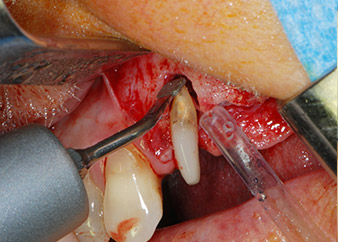

However, we maintained our initial plan to retain both teeth as temporary bridge abutments during the six-months osseointegration period of the implants. At reentry, the situation would have to be reassessed. First, in an attempt to manage the endo-perio problem, the remaining root surface was carefully debrided with piezoelectric equipment (Piezomed, W&H, used with the spatula-shaped insert S1, originally designed for erosion of the lateral sinus wall) (Fig. 4).

periodontium

Fig. 4: To preserve the tooth as a temporary abutment, the periodontium was debrided with piezoelectric equipment …